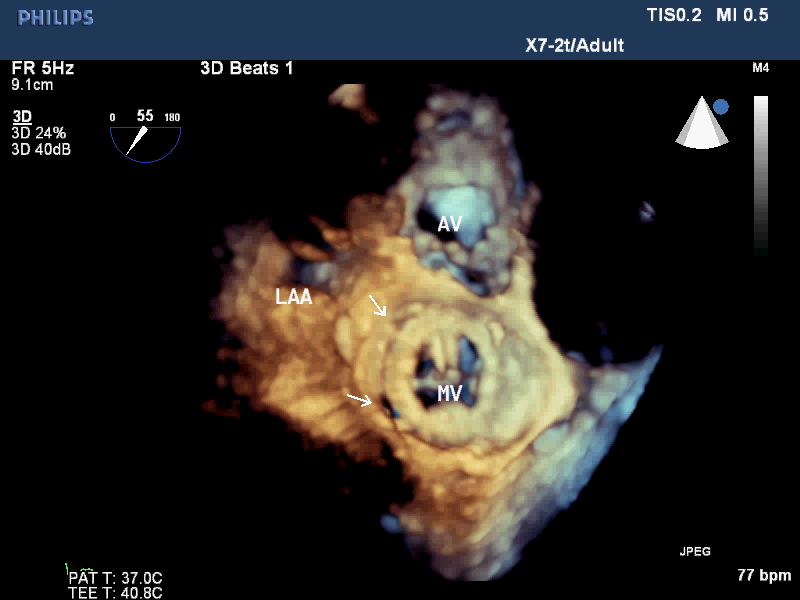

术前超声检查

超声提示:主动脉瓣狭窄并关闭不全,PGmax42mmHg,返流8ml,三叶瓣,钙化轻,EF47%。二尖瓣瓣周漏(两处8点,10点),较大返流10ml,三尖瓣关闭不全(中度),肺动脉高压(PGmax48mmHg)。